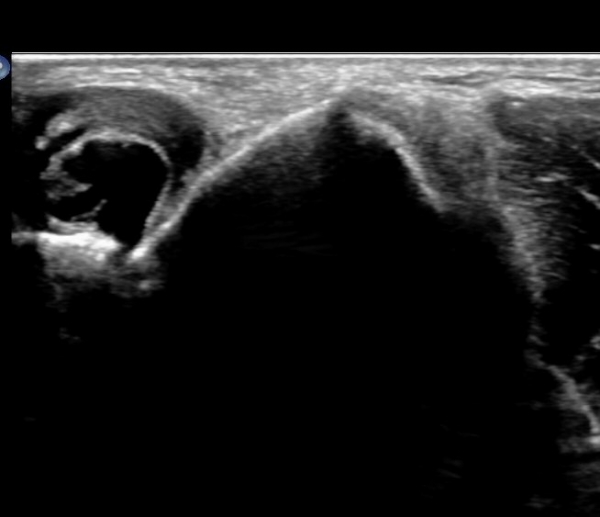

ÆÈ²ÞÄ¡ µÚÂÊ Á¾´Ü¸é°Ë»ç¿Í Ⱦ´Ü¸é°Ë»ç¿¡¼­ ÁֵοÍ(olecranon fossa)¿¡ ¼ö¾×Àú·ù°¡ °üÂûµÊ(»çÁø 1, 2)